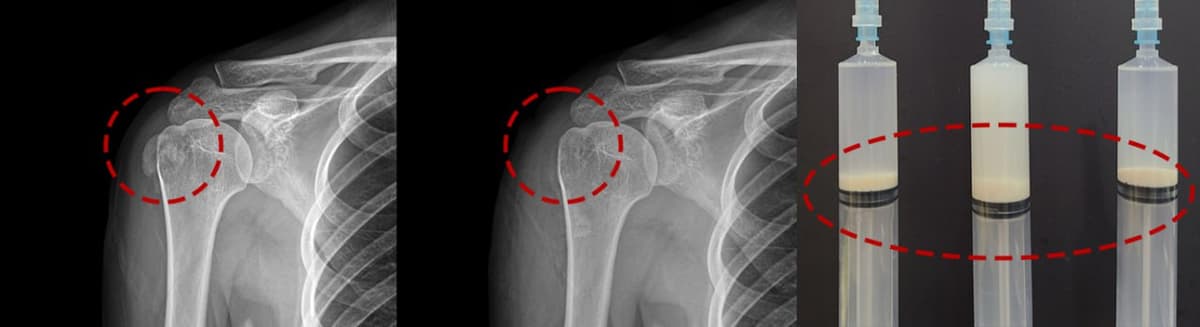

시술 전후 X-ray 비교

단단한 석회도 1회 시술 후 완전 제거. 실제 환자 X-ray입니다.

X-ray상 어깨 힘줄에 하얀 석회 덩어리가 선명하게 보입니다.

1회 석회분쇄흡입술 후 석회가 완전히 제거된 것을 확인할 수 있습니다.